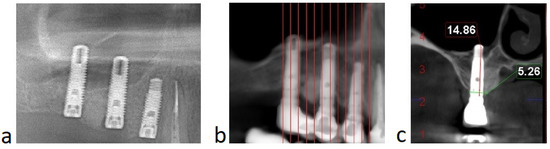

All patients from the group presented successful outcomes with respect to implant integration and sinus augmentation procedures. They exhibited reduced, or even no, pain after surgery, and minimal discomfort due to edema. Clinical evaluation of the surgical site revealed good healing, with normal color and texture of the soft tissue. Signs of infection, dehiscence or inflammation were absent for all nine patients (100%). Implant uncovering demonstrated good osseointegration, with no mobility and no vertical bone loss. Implant survival was assessed every 6 months for 1 to 4 years, with a mean follow up of 1.8 years, after the prosthetic loading. Radiological examinations were performed on CBCT at 9 and 12 and 36 months postoperatively and revealed improved degrees of radiopacity from the first to the last CBCT. The first radiological examination showed a homogenous radiopacity of the PRF membranes with a net delimitation from the sinus cavity. Months later, the implants appeared to be surrounded by a dense bony-like structure, with no peri-implant radiolucency (Figure 6). The apices of the implants, as well as 1 mm below the tip of the implant, showed no bone formation due to the fact that the membrane is leaning on it.

Figure 6. (Case no. 4) Radiological aspect of the sinus floor augmentation performed with PRFs, with different degrees of radiodensity: immediately after the surgery (a); and 12 months after the procedure (b). Specific image of sinus augmentation with PRF where the tip of the implant (1–1.5 mm) has formed no bone, due to Schneiderian membrane pressure during the new bone formation process (c).